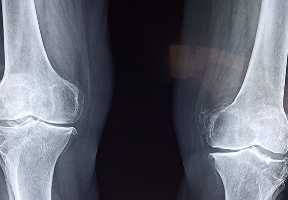

콘드로이친 효능 및 부작용 등 콘드로이친과 관련된 정보 알아보도록 하겠습니다. 콘드로이친은 관절의 연골을 보호하고 재생하는 데 도움이 되는 물질입니다. 콘드로이친의 결핍은 관절염이나 퇴행성 관절질환과 같은 질병의 원인이 될 수 있습니다.

1. 관절염 예방 및 완화: 콘드로이친은 관절염의 주요 원인인 연골의 손상을 방지하고, 연골의 재생을 도와줍니다. 콘드로이친은 또한 염증을 감소시키고, 통증을 줄여줍니다. 여러 연구에서 콘드로이친 보충제가 관절염 환자의 증상을 개선하는 데 도움이 되었다고 보고되었습니다.

2. 스포츠 부상 회복: 콘드로이친은 스포츠 활동으로 인해 손상된 관절과 연골의 회복을 촉진합니다. 콘드로이친은 관절의 윤활을 개선하고, 연골의 탄력성을 높여줍니다. 콘드로이친 보충제를 복용하는 것은 스포츠 부상의 치유 시간을 단축하고, 재발 위험을 감소시킬 수 있습니다.